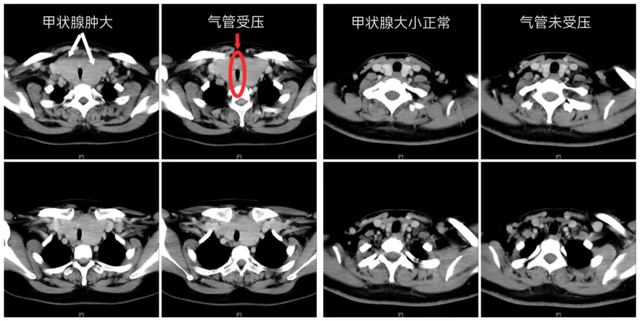

影像检查结果令人心惊

气管被挤压成“细线”

术后6小时,王女士即恢复清晰发声,可自主进食流质食物,四肢活动自如。“呼吸终于不费劲了。”她对着镜子看着平坦的颈部,声音仍带着些许沙哑,却掩不住眼底的欣喜。术后影像复查显示,原本被挤压成“细缝”的气管已恢复通畅,这颗困扰她十余年的“生命腺”重荷被成功卸下。